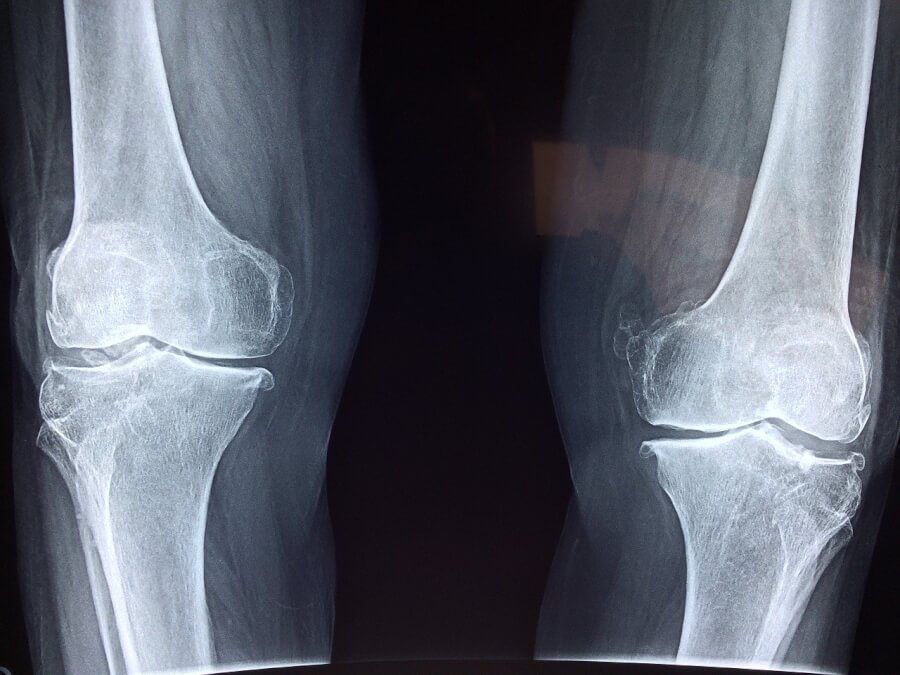

この炎症は関節の端を覆う軟骨にまで広がり、不可逆的な損傷と機能喪失を引き起こす可能性があります。また、肺、心臓、腎臓、皮膚、目などの他の組織にも損傷を与える可能性があります。

関節リウマチは関節間の組織に炎症を引き起こします。これにより、関節のクッションとなる結合組織である軟骨が失われます。時間が経つと、軟骨の喪失により関節や近くの骨が損傷する可能性があります。